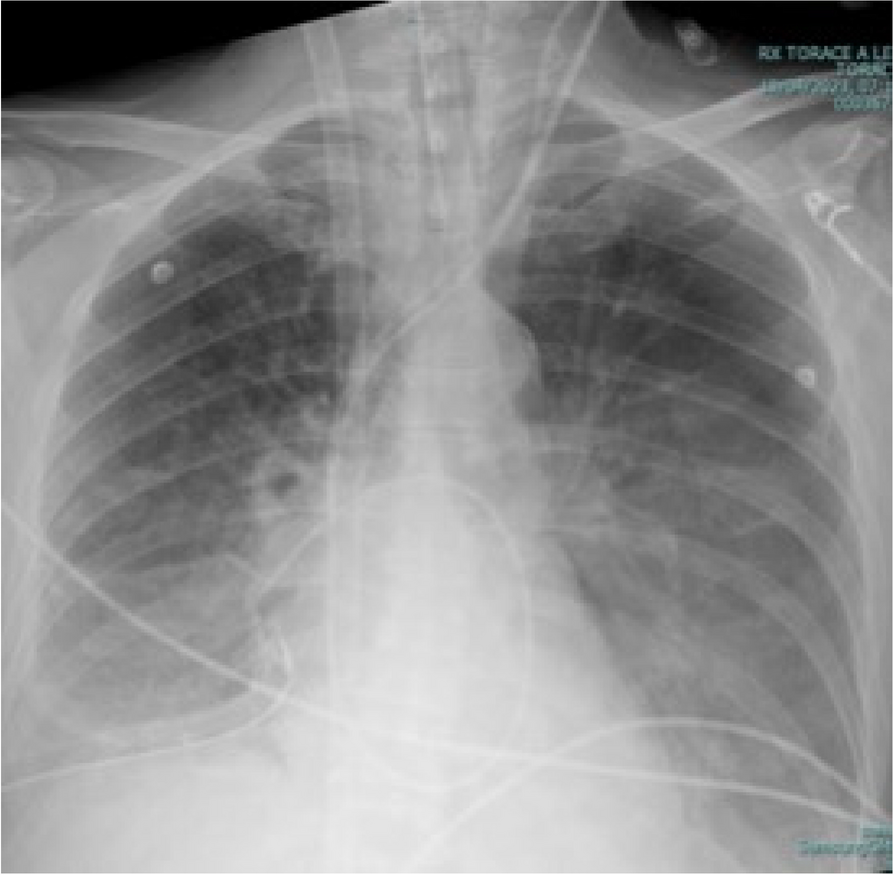

A9 Non-invasive respiratory support in endoscopic surgery with High Flow Nasal Cannula in patients affected by Legionella Pneumophila: a case report

A. Scalvenzi, M. Del Prete, M.E. Porcelli, F. Coppolino, V. Pota, P. Sansone, M.B. Passavanti, M.C. Pace

Università degli Studi della Campania L. Vanvitelli, Napoli, Italy

Correspondence: A. Scalvenzi

Journal of Anesthesia, Analgesia and Critical Care 2023, 3(Suppl 1):A9

Introduction

Legionella Pneumophila is one of the most important causes of respiratory infections in humans and it is the cause of about 30% of nosocomial infections.

Anastomotic leakage following the intervention of esophageal resection presents one of the surgical complications with the highest morbidity and mortality.

Case reports

For the past year we have faced a case of anastomotic leakage post esophageal resection, treated through the application of an endoprosthesis esophageal in a patient affected by L. Pneumophila.

The main problem for the anesthetist during this procedure is identifying the most inadequate perioperative management.

In this specific case, the patient, affected by L. Pneumophila, presented a PO2/FiO2 ratio between 100mmHg and 200mmHg, giving rise to a moderate ARDS panel according to Berlin Criteria (Image 1).

For this reason, we decided to use a non-invasive periprocedural ventilation mode, specifically the High Flow Nasal Cannula (HFNC), to reduce the risk of postoperative pulmonary complications due to invasive ventilation through endotracheal intubation (ETI).

The parameters set during the entire procedure remained stable: Flow 60 L/min, FiO2 100%, Temperature 37 °C.

The patient, opportunely mixed with the current type of anesthesiological procedure and immediately after signing the Informed Consensus, is premedicated with intravenous Midazolam 0.05mg/Kg, while sedation is effected with an initial bolus of Propofol at 0.5mg/Kg. Successively, sedation is maintained whit Propofol in continuous infusion at 3.5mg/Kg/h.

The approximate duration of the procedure is 25 minutes. The patient's vital parameters are stable for all the duration of the intervention, with a SpO2 > 95%, and a MAP > 70 mmHg.

After the procedure, the patient is returned to the Intensive Care unit where he has completed the course of antibiotic therapy, with a progressive reduction of the need for oxygen therapy.

Conclusion

Airway management in patients with L. pneumophila can be a problem, aggravated by a series of additional risks related to ETI, such as pulmonary damage from mechanical ventilation, contamination of the ventilator, delayed weaning and an increase in hospital stay days. The use of HFNCs in endoscopic procedures allows to avoid these risks, eliminating the operating field conflict with the surgical procedure and guaranteeing a higher oxygen saturation compared to other oxygenation devices.

Image 1 (abstract A9).

See text for description

Bild vergrößern